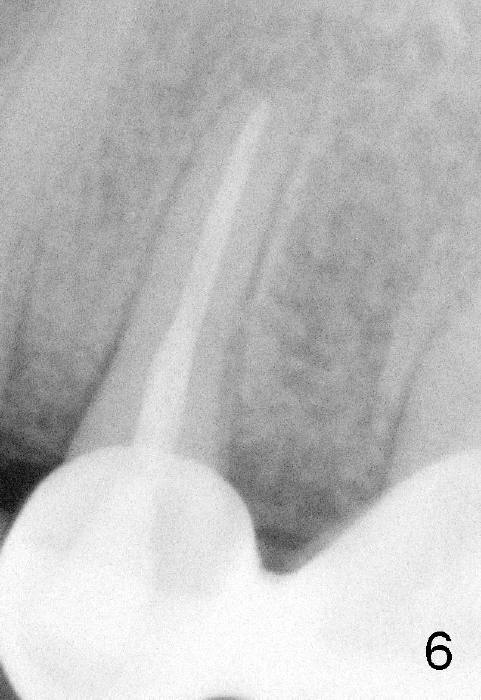

图二显示我们已经打开根管(灰色部分),黑线代表陶瓷牙金属部分,一旦水接触金属,Apex locator就不好用了。如果我们有一种方法使根管中水(图三红色)低于金属,Apex locator就能施展本领。我们在根管开口处插入外科吸管(图三绿色),水可以很快吸掉,水不再接触陶瓷冠金属。